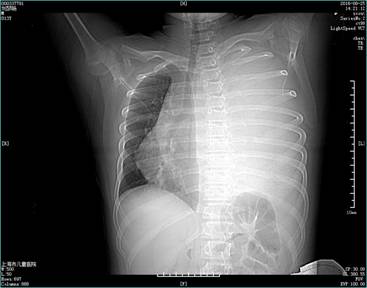

近日,一名十岁男童检查出胸腔内有20cm×15cm×5cm巨大肿瘤,这个和一部电话座机差不多大小的肿瘤几乎占满了孩子整个左侧胸腔,并与周围的身体组织发生粘连,辗转多家医院后收治于上海市儿童医院进行手术。手术历时5小时,经过肿瘤切除术、肺叶修补术、胸膜剥脱术、膈肌折叠术等多个手术,成功切除了这个压在患儿一家心上的“包袱”。

三个月前小文突然开始出现没缘由的呼吸急促,尤其是在上楼梯或者运动的时候,仅仅是小幅度的活动也会让他气喘吁吁,但家长一直没有当回事,直到半个月以前,症状一直没有缓解,家人便带他到当地医院做了各项检查,通过穿刺活检发现,小文的左侧胸腔里有一个巨大的恶性肿瘤,几乎占满左侧胸腔,导致肺部和心脏受到了挤压,这也就直接引发了小文呼吸急促。他的肿瘤对放疗、化疗均不敏感,必须手术切除,但由于当地医疗条件有限,并且在诊治的过程中,小文开始出现反复发热,心急如焚的家人果断决定带着小文找上海市儿童医院的专家诊治。

左侧胸腔肿瘤将心脏都挤压“挪位”

上海市儿童医院心胸外科主任张儒舫收治了小文,凭借多次切除胸腔巨大肿瘤手术以及丰富的心胸外科手术经验,快速为小文进行了敲定了手术时间。报告显示,小文胸腔内肿瘤尺寸约20cm×15cm×5cm,约是一个家用座机电话的大小,在胸腔内与心脏、肺、膈肌等组织粘连,其中与肺粘连的程度最深,从而导致此次手术难度巨大,因为稍有不慎就会触及到肺及其周围的血管和神经,从而引起各类严重的术后并发症。此外,由于肿瘤与肺融合粘连严重,与胸腺、膈肌、心包融合粘连,因此这不只是一个简单的肿瘤切除手术,还要完成肺叶修补术、胸膜剥脱术、膈肌折叠术等多项手术。手术于当天下午三点半正式开始,一直持续到晚上8点才结束,历时5个小时,对于医生的专业能力和体能都有一定的考验。值得庆幸的是肿瘤的存在并没有影响到小文其他脏器的功能,粘连严重的左肺功能良好,现如今卸下胸中“包袱”的小文已经出院,进入了康复阶段。